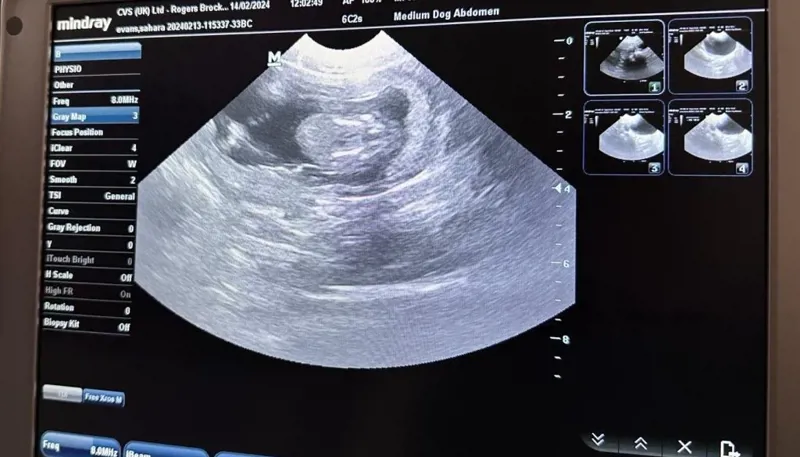

![PHOTO 2024 02 14 13 03 44 1024X585]()  FIRST EVER ULTRASOUND on Barbary macaque at UK Monkey Forest REVEALS she is PREGNANT!7th Mar 2024 Trentham Monkey Forest has successfully carried out its first-ever ultrasound examination on a monkey called ‘Pretty’ and discovered that she is in fact, PREGNANT!